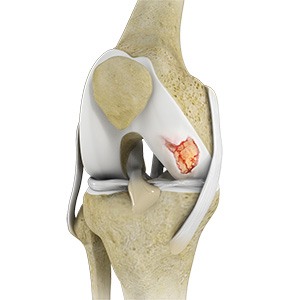

Cartilage Microfracture

Cartilage microfracture is a surgical procedure performed to replace the worn-out articular cartilage with new cartilage.